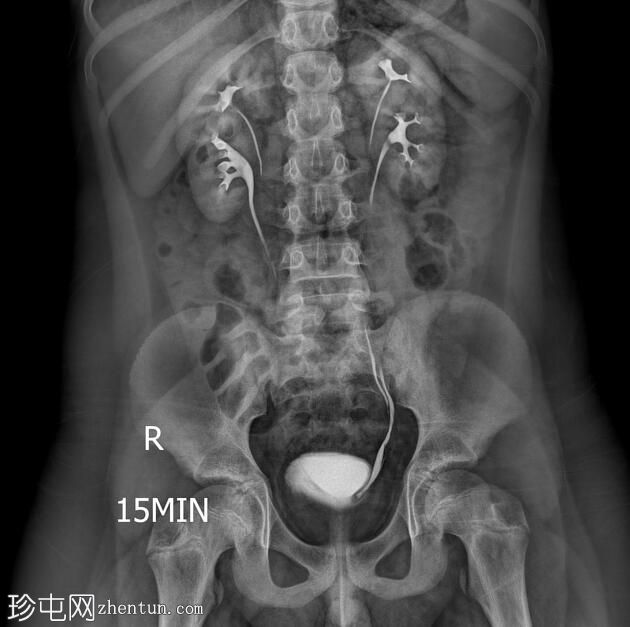

透视检查

正位

双侧肾盂肾盏系统及输尿管重复畸形。

左肾上极异位输尿管末端形成输尿管囊肿。

根据魏格特-迈耶定律,在完全性输尿管重复畸形的双肾病例中,上极和下极分别由独立的输尿管引流。上极输尿管通常存在异位开口,位于下极输尿管的内侧和下方,并常形成输尿管囊肿,正如本病例所示。